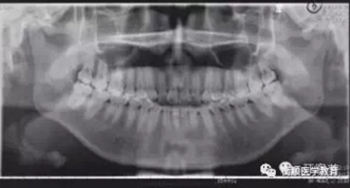

圖3 治療前曲面體層片